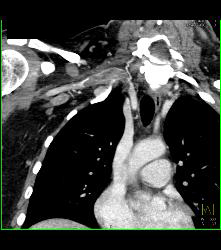

Cervical Rib With Occlusion of the Right Subclavian Artery- See Full Sequence